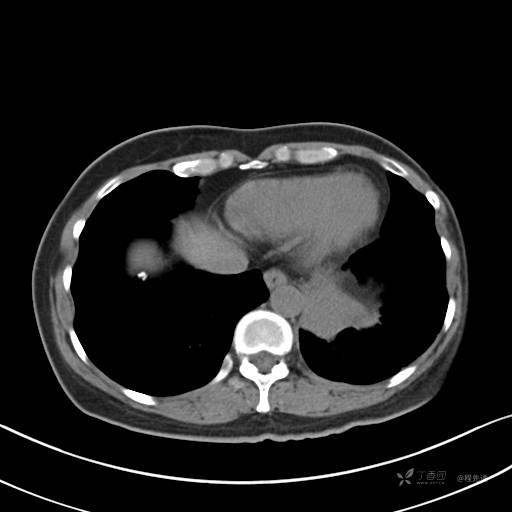

肺窗

增强动脉期

动脉期CT值约74HU